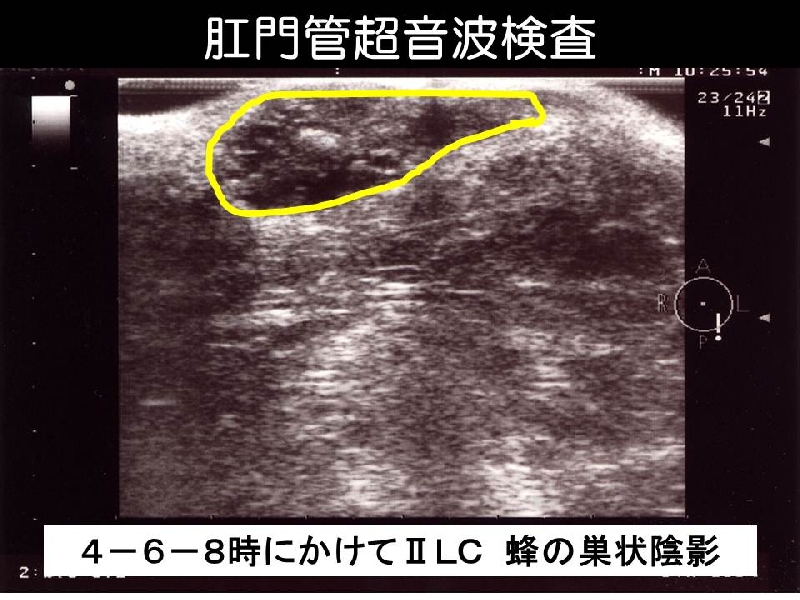

Mucinous adenocarcinoma associated with chronic fistula in ano is rare, and diagnosis is often difficult. Four cases of mucinous adenocarcinoma arising from longstanding anal fistulas are presented. Endoanal ultrasonography (SSD-Prosound 4000, ALOKA, Tokyo) revealed characterisric features; those consist of a hypoechoic bulging lesion containing heterogenous hyperechoic spots with “ honey comb appearance”. This is due to the fact that mucinous adenocarcinomas usually contain many small mucous lakes. This finding shows the implications in diagnosing mucinous adenocarcinoma arising from fistula in ano.